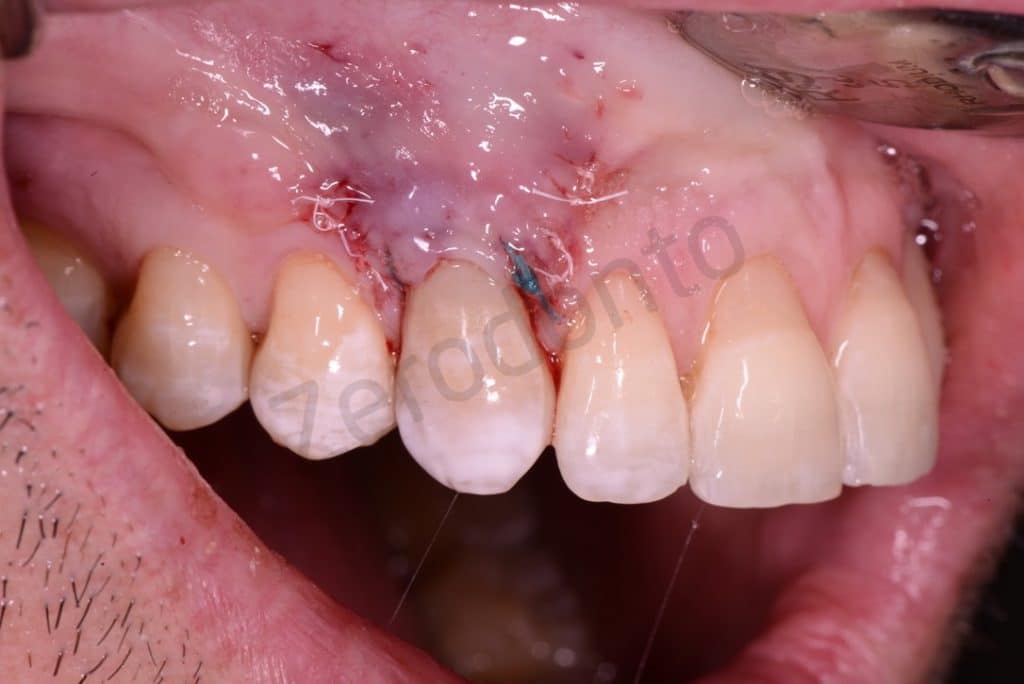

A coronal repositioning flap first at partial thickness then total thickness and finally a periosteal incision to mobilize the flap were performed. The anatomical papillae were disepithelized to allow the sliding of the surgical papillae.

Flap

The lesion

Detail of the lesion